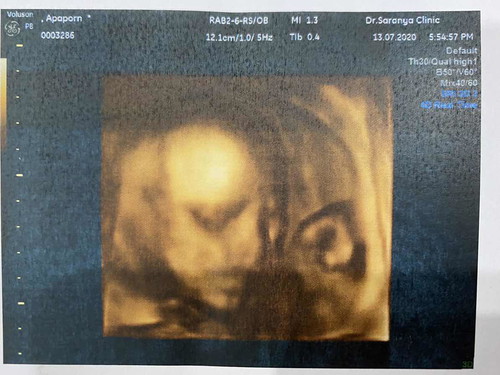

6 เดือนแล้วคะ ได้ลูกชาย อยากรู้ว่าซาวด์ตอน 7-8 เดือนจะชัดกว่านี้อีกไหม คุณหมอตอบว่าชัดกว่านี้แน่นอนคะ นี่แม่ก็ว่าชัดแล้วนะ

สันจมูกน้องงงมาแรงมากค่ะแม่